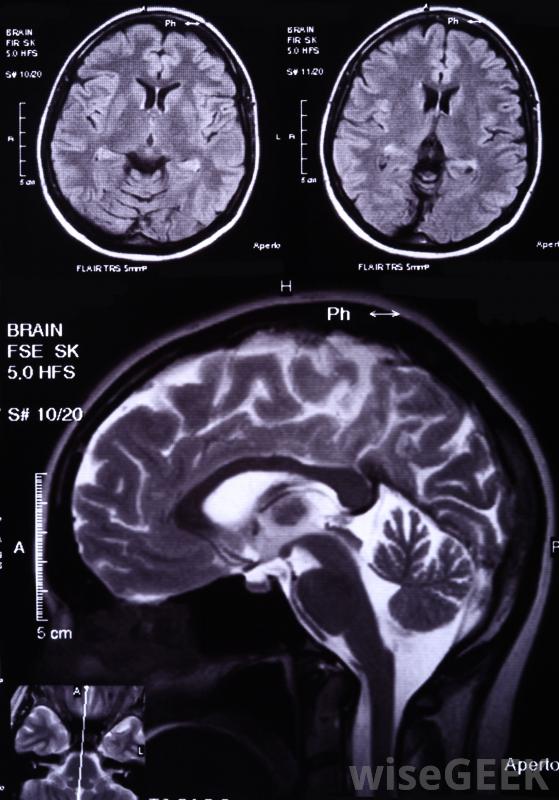

母細胞瘤是起源于胚胎組織的任何腫瘤的總稱,因此通常指兒童癌癥。母細胞瘤一詞通常作為特定腫瘤的醫學全稱的一部分,如髓母細胞瘤、神經母細胞瘤或胸膜肺母細胞瘤,母細胞瘤的預后或預期的醫療結果會因腫瘤的具體類型和位置而有所不同胚胎瘤這個詞出現在各種各樣的兒童癌癥的醫學名稱中。膠質母細胞瘤和髓母細胞瘤是指腦瘤。肝母細胞瘤是肝臟的一種腫瘤,腎母細胞瘤是一種影響腎臟的腫瘤。胸膜肺母細胞瘤是一種罕見的影響肺部的癌癥。其他常見的兒童癌癥包括視網膜母細胞瘤,它影響眼睛;神經母細胞瘤,起源于腎上腺或神經系統的相關部分;以及成骨細胞瘤,母細胞瘤是一種見于骨組織的良性腫瘤髓母細胞瘤是一種兒童腫瘤,起源于小腦,位于大腦下部,可能沿脊柱或特定骨骼轉移,這類腫瘤通常可以通過放療和手術治療,有時也用輔助化療,預后很好,膠質瘤和髓母細胞瘤是指腦腫瘤神經母細胞瘤是一種影響腎上腺和神經系統的腫瘤,是兒童和嬰兒最常見的非腦源性腫瘤,其癥狀包括眼周黑眼圈或眼球腫脹,如果腫瘤壓迫脊髓,就有可能癱瘓。在大多數情況下,神經母細胞瘤腫瘤在轉移后才被診斷出來;這種情況通常在出生時出現,但直到嬰兒期或兒童期才被發現